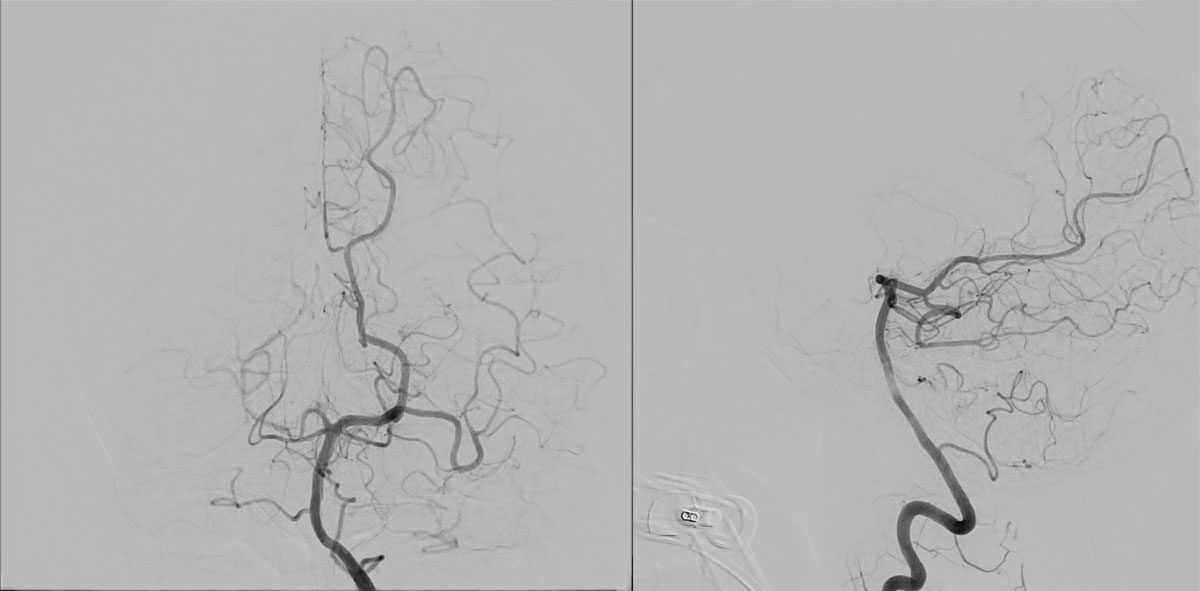

DSA

EVT Strategy

• Inflate the balloon, in order to dilate the true lumen

• MCA access with the softest system possible

• Open a stentriever for 20 mins with antiplatelet infusion

• Resheath the stentriever, check patency, if not stent-deployment

Headway™ DUO 156cm / Traxcess™ 14

CatchViewMini20

pEGASUS 4x20mm